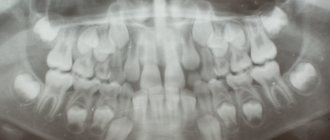

В большинстве случаев стоматолог определяет причину состояния визуально или после опроса пациента. Однако иногда для уточнения диагноза требуются дополнительные исследования:

• томография черепной коробки;

• допплерография сосудов;

• рентген челюсти.

Грамотное лечение невозможно без установления точной причины синдрома, поэтому если врач назначает диагностические процедуры, не стоит от них отказываться, без этого эффективность терапии может быть заметно снижена.